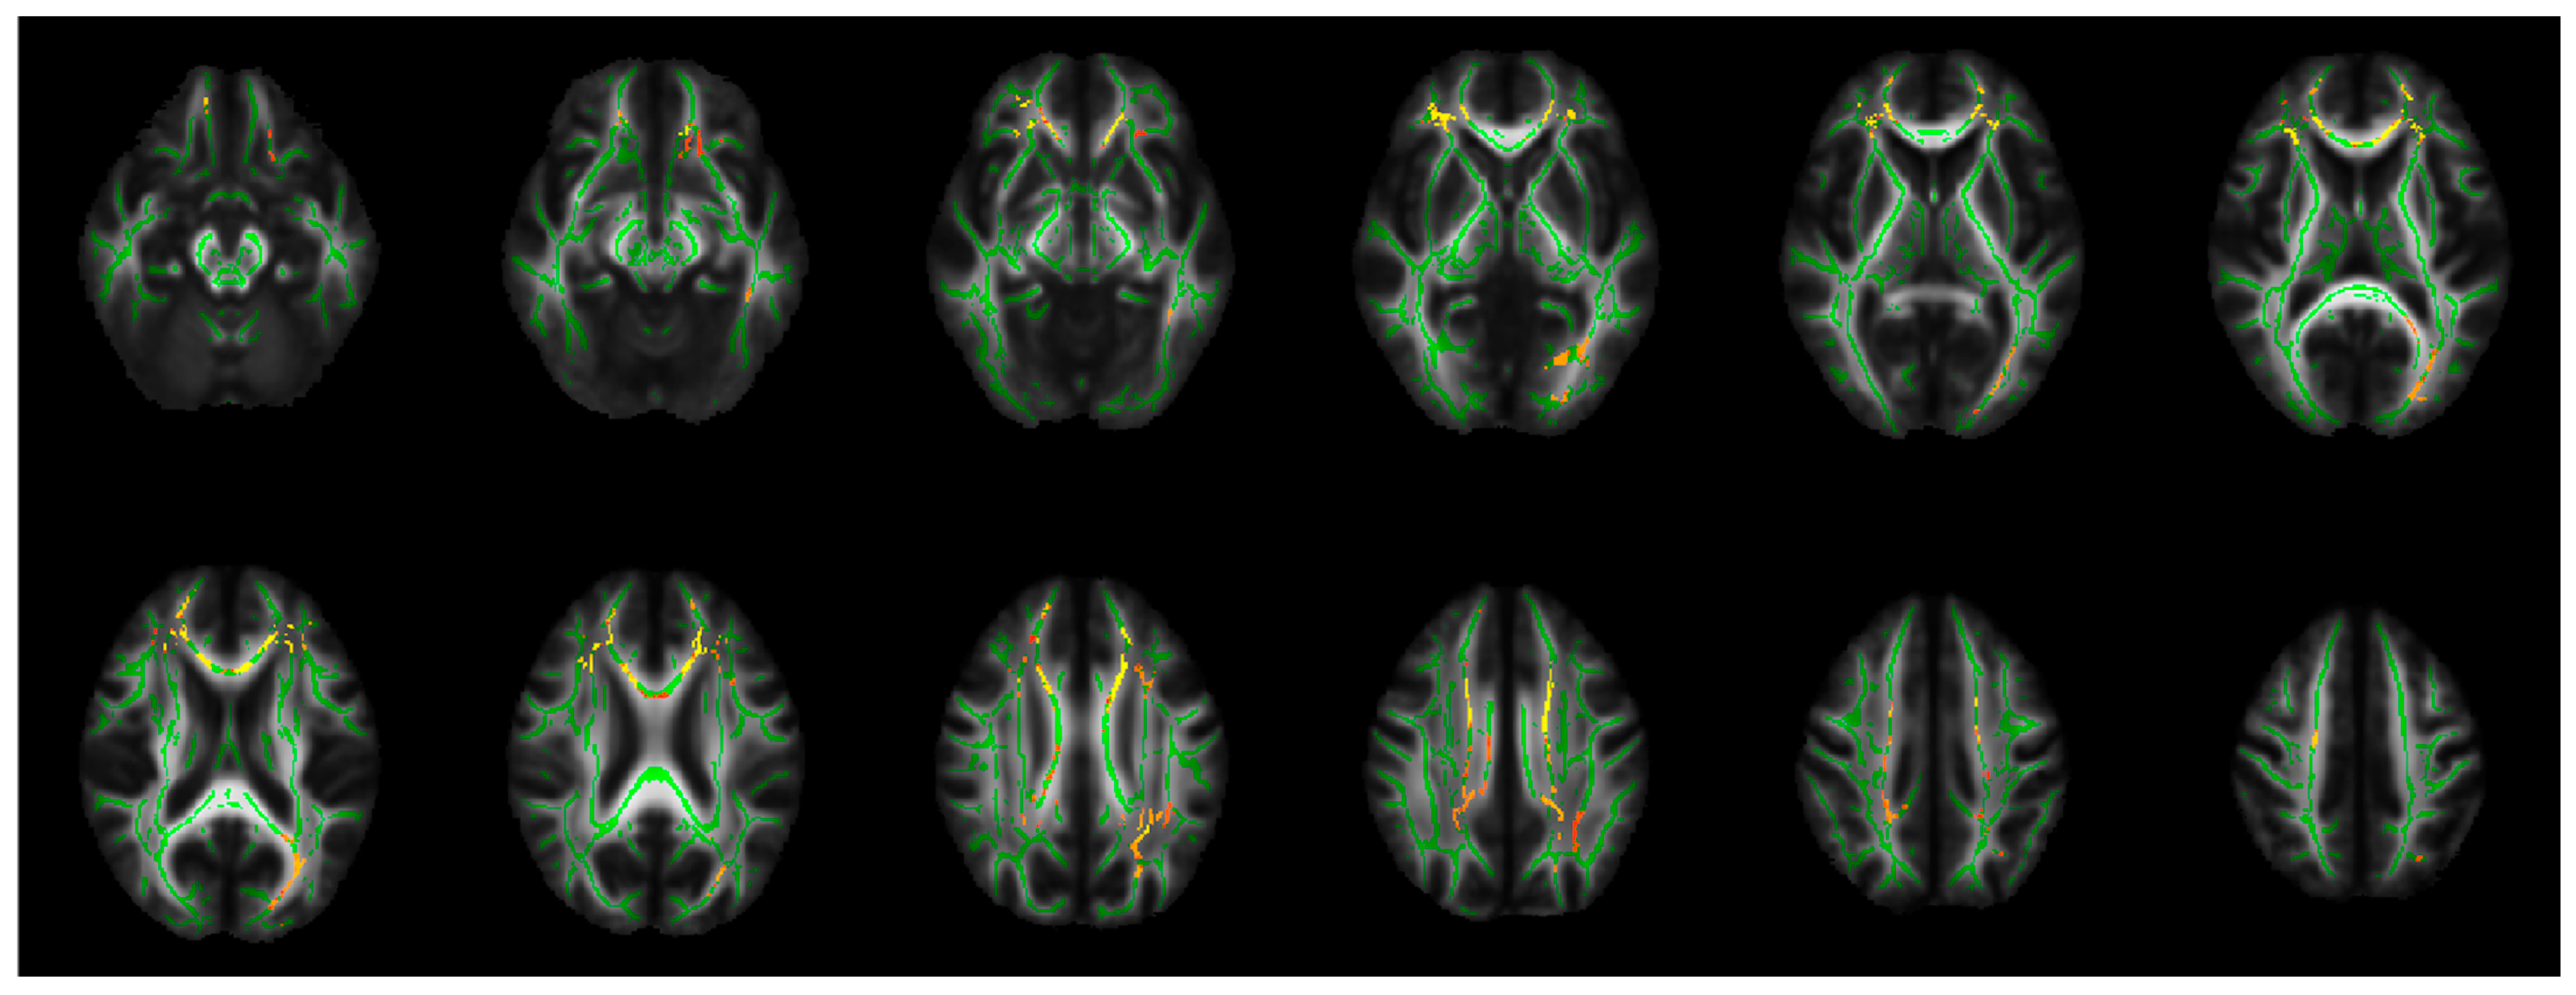

3.2. TBSS Analyses

| Increased RD (ptfce-FWE < 0.008 **) | Bilateral orbitofrontal cortex WM, Fmin, gCC, bCC, ACR, SCR, PCR, anterior cingulum, inferior frontal WM, bottom part of the superior parietal lobule WM, posterior part of the superior longitudinal fasciculus, and posterior cingulum The left posterior part of the inferior fronto-occipital fasciculus and ILF, posterior thalamic radiation, optic radiation, lingual gyrus WM, splenium of the CC, forceps major, and the temporal part of the IFL |

| Increased RD (ptfce-FWE < 0.014 *) | Left Fmin, gCC, bCC, and ACR |